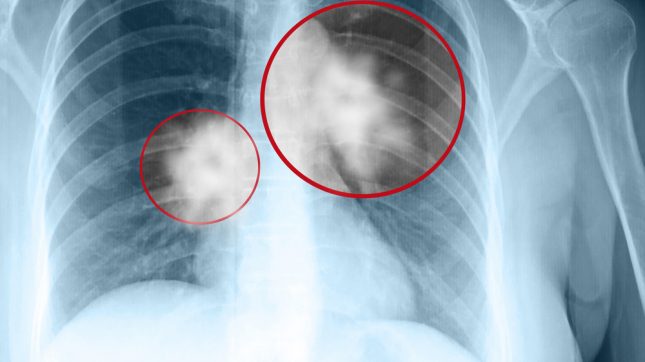

הטיפול בסרטן ריאות שלב 3 ממקור תאים שאינם קטנים (NSCLC) שאיננו נתיח כרוך בעיקר בכימו-ארדיקציה (concurrent chemoradiation CRT). טיפול קונסולידציה לאחר CRT באמצעות durvalumab מהווה התקדמות טיפולית משמעותית המספקת יתרון הישרדותי בקבוצה זו של חולים. עם זאת, טרם דווח על הביצועים של אסטרטגיית טיפול זו במסגרת טיפול אמיתית מחוץ למחקרים הקלינים.